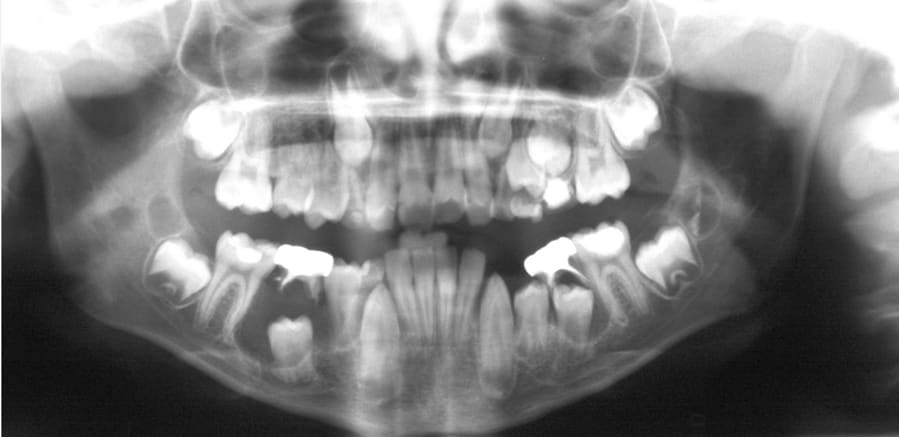

Dentigerous cysts are the second most common type of odontogenic cyst, which is a fluid-filled sac that develops in the jaw bone and soft tissue. They form over the top of an unerupted tooth, or partially erupted tooth, usually one of your molars or canines. While dentigerous cysts are benign, they can lead to complications, such as infection, if left untreated.

While anyone can develop a dentigerous cyst, they’re more commonTrusted Source in people who are in their 20s or 30s.

How is it diagnosed?

Small dentigerous cysts often go unnoticed until you have a dental X-ray. If your dentist notices an unusual spot on your dental X-ray, they may use a CT scan or MRI scan to make sure it’s not another type of cyst, such as a periapical cyst or an aneurysmal bone cyst.